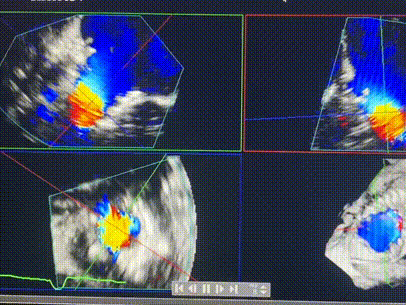

術前超聲提示重度三尖瓣反流

術中輸送器在超聲引導下調整位置